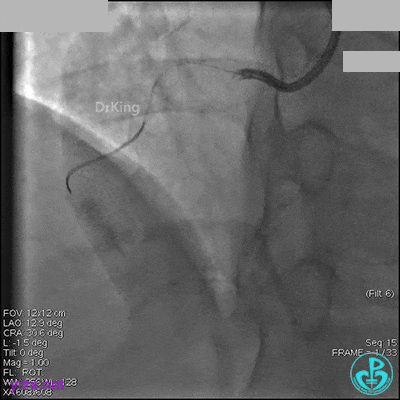

右冠脉中段充分扩张后欲植入3.5×38mm支架时,支架难以通过中远段扭曲处,且指引导管、导丝弹出飞扬。反复尝试导丝重新到达右冠脉远端时通过不顺利,局部造影剂滞留,远端血流接近3级。

右冠脉血流3级,患者无症状,终止手术。